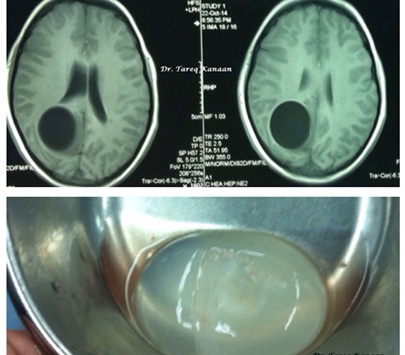

نجح فريق طبي في مستشفى الجامعة الأردنية باستئصال كيس مائي سببه الدودة الشريطية المقنفذة من

دماغ طفل يبلغ من العمر ثلاثة عشر عاما.

وقال جراح الدماغ والأعصاب الدكتور طارق كنعان الذي

أجرى العملية في تصريح لـ خبرني، إن الفريق نجح باستئصال كيس مائي سببه الدودة الشريطية المقنفذة (Hydatid Cyst) من دماغ الطفل الذي كان يعاني من صداع حاد مع تشوش في البصر وضعف في الطرفين السفليين

مما سبب له عدم القدرة على الوقوف والمشي.

وأجريت العملية الشهر الماضي، بنجاح كامل لا

سيما وأن إجراء مثل هذه العمليات بالغ الخطورة، وتكمن خطورتها في احتمال انفجار الكيس

المائي داخل الدماغ مما يؤدي الى انتشار آلاف البويضات التي بداخله في الدماغ والنخاع

الشوكي لتكون النتيجة عشرات الأكياس الجديدة التي يستحيل استئصالها، ما يعني فرط الحساسية

التي عادة ما تنتهي بوفاة المريض أثناء العملية.

استئصال الكيس بالكامل دون انفجاره في عملية استغرقت ثلاث ساعات.